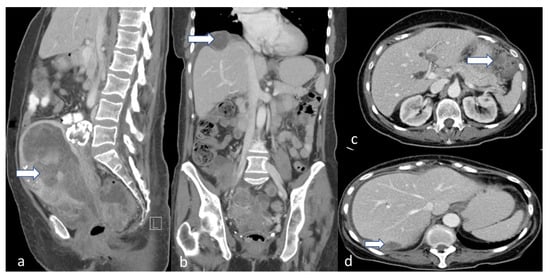

5.2. Computed Tomography (CT)

4.4. Stage IV

5.3. Magnetic Resonance Imaging (MRI)